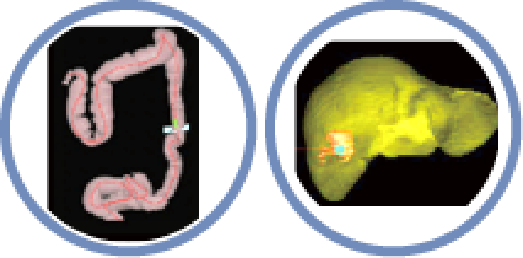

Precision in Oncology

▪ Liver Analysis

▪ Pelvic Masses